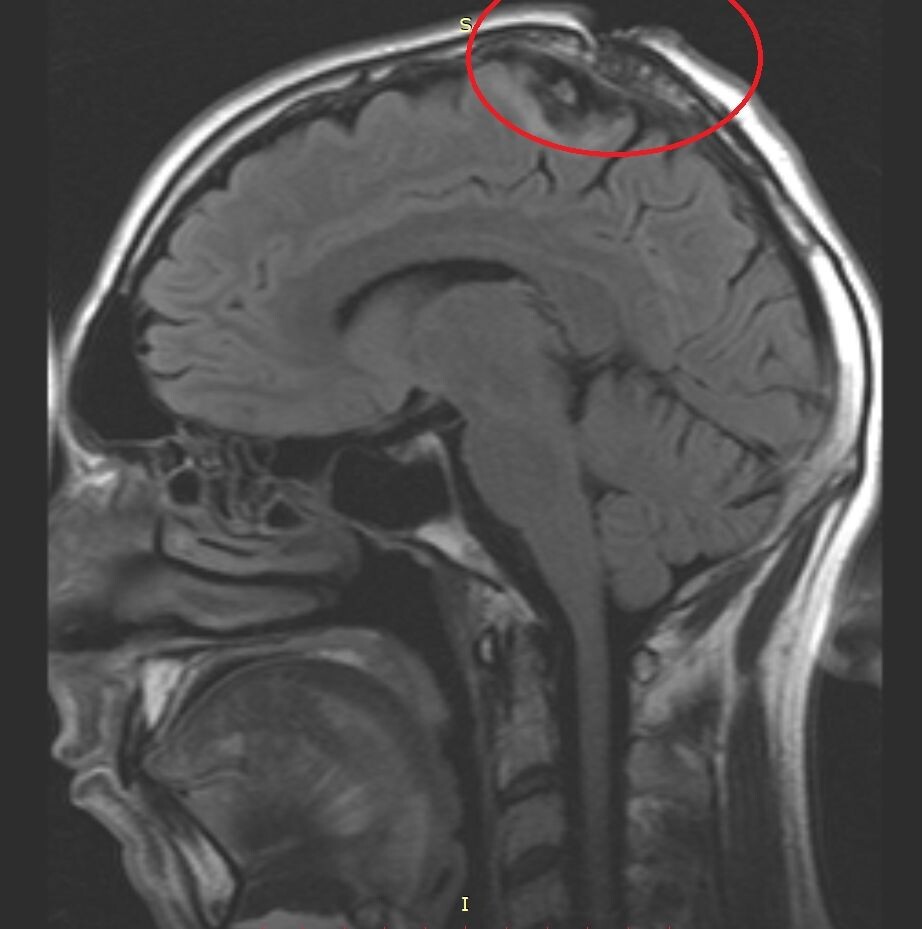

МРТ головы в боковой проекции. На МРТ-снимке визуализируются последствия боевого ранения: металлический осколок и костные фрагменты в теменной области слева (практически по продольной щели головного мозга). При таком серьезном ранении твердая мозговая оболочка осталась неповрежденной — это во многом определило тактику лечения.